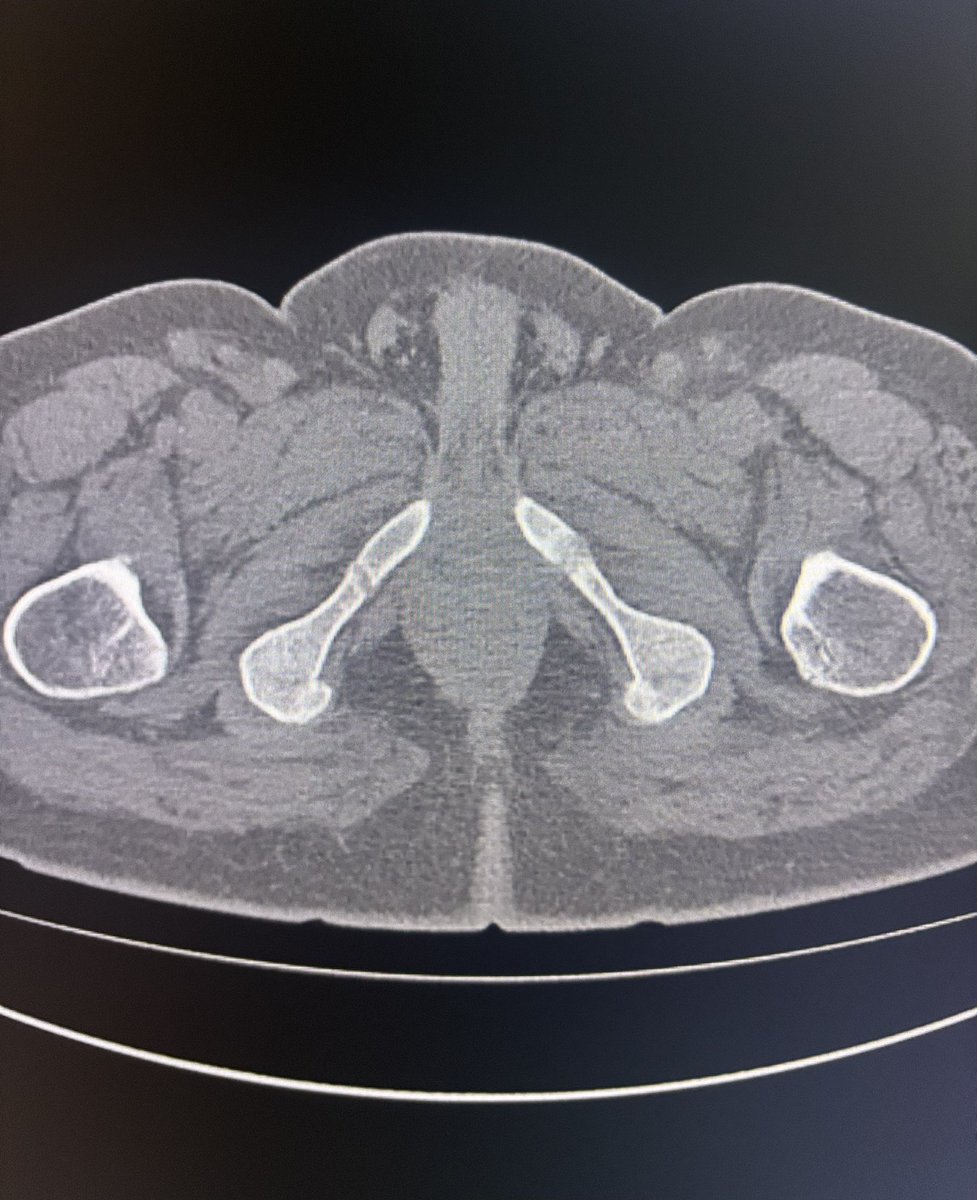

36 year old male with hip pain since 20 days.

What is the most likely diagnosis?

#Orthotwitter

#MSKradiology